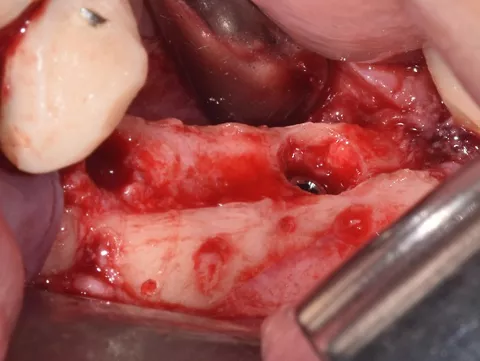

2. Incision and detachment of anatomical structures, highlighting of the inferior dental nerve at the level of its emergence from the mental foramen. 3D bone atrophy is noted. Tissue relaxation is achieved by periosteal incisions in order to release tension and close the site properly.

3 . Split bone block technique using autogenous cortical plates taken from the left ramus according to F. Khoury's protocol.

One buccal plate and one lingual plate are positioned and osteosynthesised with 1 mm Stoma screws.